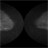

- Fundus autofluorescence imaging of a patient with autosomal recessive Best disease